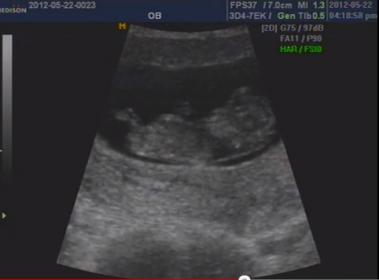

Guess for a friend!